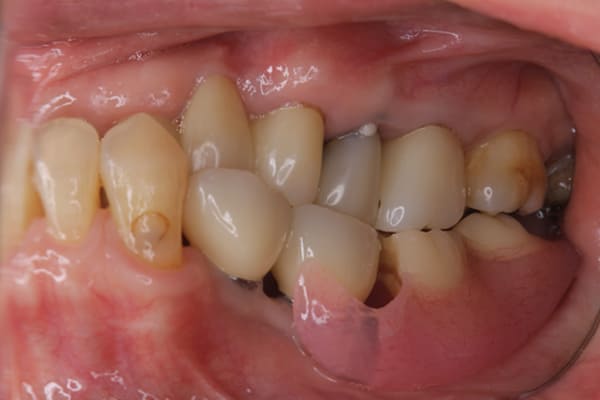

上の前歯が重度歯周病により動揺し、残せない状態のため、入れ歯も動揺がありました。

ご自身の歯に負担の少ないバネ、また見た目も改善

ご自身の歯に負担の少ないバネ

銀歯からセラミック歯に

バネをかける歯は繋げることで強度を増し、歯への負担を軽減し、歯の寿命を長くする設計へ。

バネがかかる歯の被せ物は、歯への負担を減らし、入れ歯が動きにくいようになる形態をあらかじめ付与することで、より入れ歯の機能が高まります。

治療を行う際、被せ物や入れ歯は、別々に考えるのではなく、一口腔単位としてお口全体のことを考え最良の治療計画を立てることが歯の寿命、機能効果を向上させるため、専門医としてこのことは常に心掛けて治療を行っています。

残りの歯に負担がかからないよう、被せ物と入れ歯の一体化を図った入れ歯

治療前は上下奥歯の入れ歯が削れていることで、かみ合わせが低くなり唇もつむった状態でした。

かみ合わせを適切な高さに戻したことで、本来の自然な口元へ。